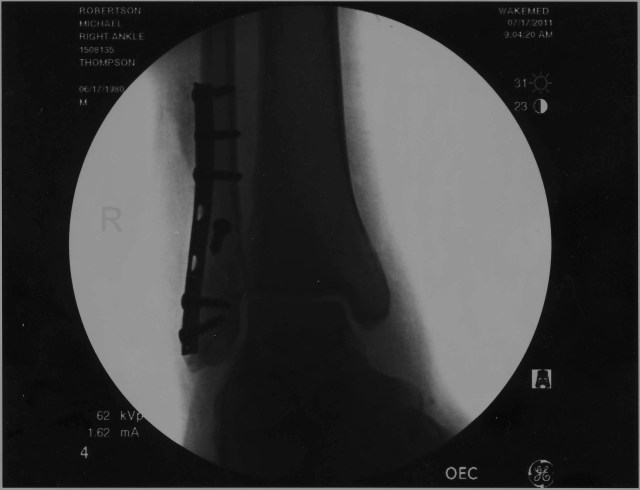

okay so this weekend was pretty intense. nathan and jeff and I went skating. i used to skate all time, now im completely out of practice. Before we hit the half-pipe we went to Vertical Urge and bougth every pad we deemed necessary: helmet, elbow pads, kneed pads, even wrist guards. well anyway none of us are experts on dropping in on the half-pipe so we’re egging each other on about who would do it first. eventually someone had to try it. i made three attempts. the first one i didnt lean forward at all and as a result fell back. the second time I was almost there. then the third attempt. on this try i dropped in and chickenfooted. i tried to catch myself but i tripped over my own ankle. anyway i dislocated my foot and broke some ankle bones. it blew. jeff and nathan took me to the emergency room. they hung out there for a few hours and then my girlfriend and parents came to take care of me. the next day my parents came and they brought me back to Charlotte. Being back in Charlotte is weird. anyway, the pics above are of the two titanium plates and screws they used to restructure my ankle. its weird i have a cast, im using crutches (which sucks), and i dont know if you can tell by my writing but they also gave me some pretty strong painkillers.